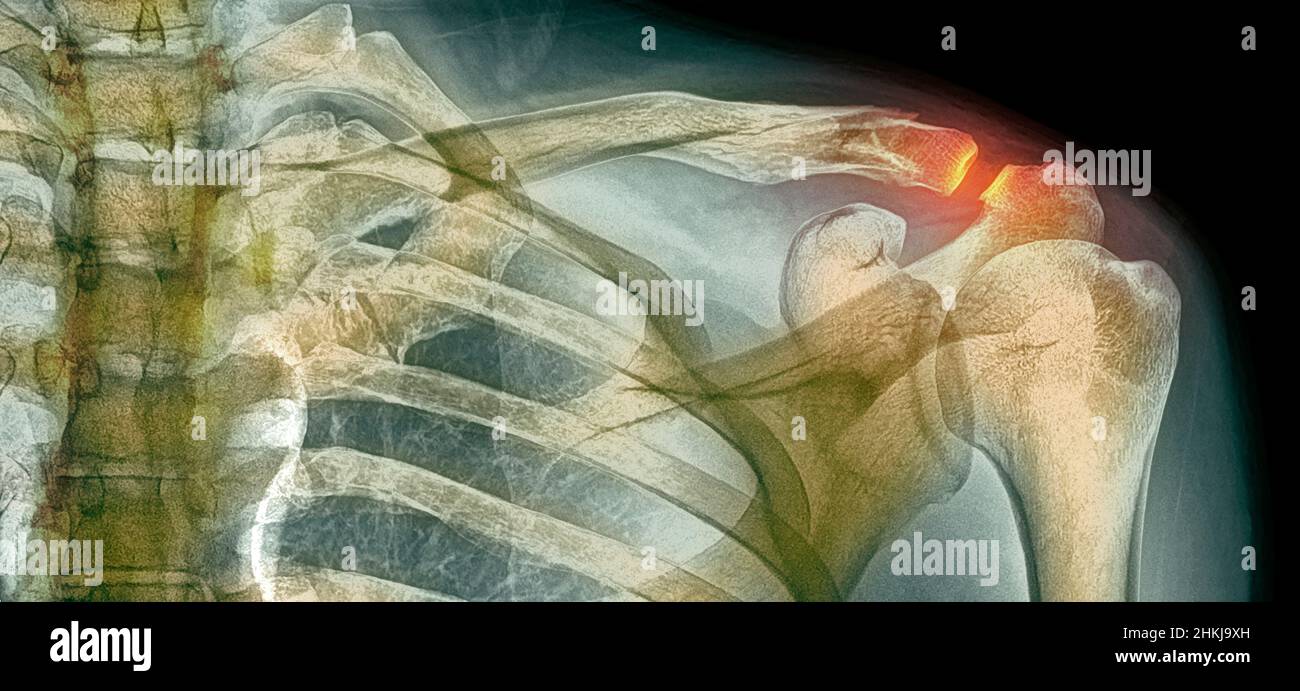

Collarbone X Ray . the clavicle (collarbone) is one of the most fractured bones in the body. To learn more about the. The ap clavicle is often indicated in patients with suspected clavicular injuries following trauma such as falling onto ones side. To help pinpoint the location of the fracture; The posterior shoulder should be in contact with image receptor (ir) or tabletop, without rotation of body. The standard ap view of the clavicle is taken with the patient upright or sitting, with arms at the sides, chin raised, and looking straight ahead. imaging of the clavicle. Symptoms of a broken collarbone include severe pain and swelling at the site of the fracture and with visible deformity in some cases. It can be requested as part of a. the radiographic series of the clavicle is utilized in emergency departments to assess the clavicle, acromioclavicular and.

the clavicle (collarbone) is one of the most fractured bones in the body. To learn more about the. The ap clavicle is often indicated in patients with suspected clavicular injuries following trauma such as falling onto ones side. To help pinpoint the location of the fracture; Symptoms of a broken collarbone include severe pain and swelling at the site of the fracture and with visible deformity in some cases. The posterior shoulder should be in contact with image receptor (ir) or tabletop, without rotation of body. It can be requested as part of a. imaging of the clavicle. The standard ap view of the clavicle is taken with the patient upright or sitting, with arms at the sides, chin raised, and looking straight ahead. the radiographic series of the clavicle is utilized in emergency departments to assess the clavicle, acromioclavicular and.

Broken collarbone or clavicle fracture signs, symptoms and treatment